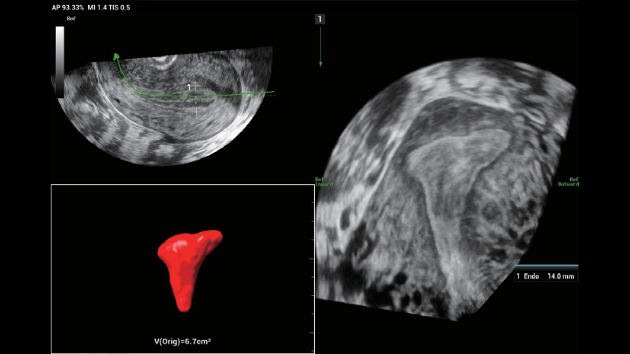

The Nuewa I9 Elite Edition, dedicatedly designed for women and neonatal healthcare, providing an innovative experience from inside out. These innovations are developed based on in-depth insights into complex clinical scenarios, providing accurate and timely answers as well as outstanding efficiency and remarkable user experience